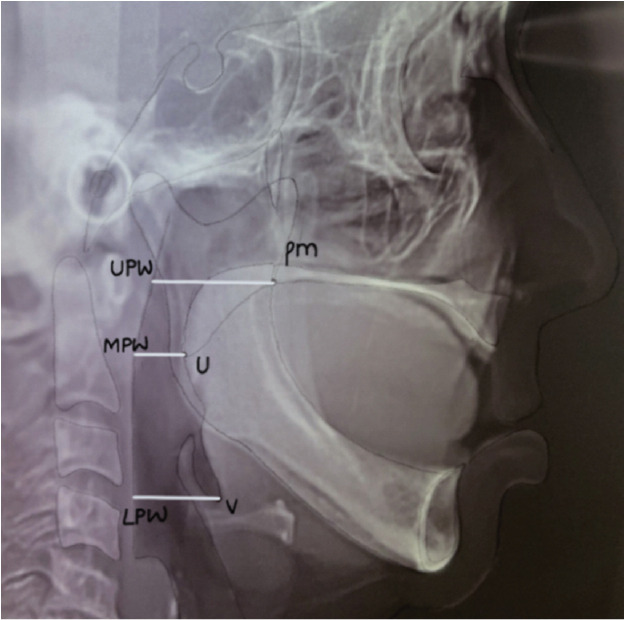

Materials and method: In this observational study, completely edentulous individuals were screened with snoring, tiredness, observed apnea, high blood pressure, body mass index, age, neck circumference, and gender (STOP-Bang) questionnaire to evaluate the incidence of OSA. Ten mild-moderate patients were included as study participants. Lateral cephalograms (L1) made at the edentulous state was considered baseline. They were rehabilitated with complete denture prosthesis. One week after denture insertion, two implants were placed in the edentulous mandibular arch. Delayed loading protocol was followed. Lateral cephalogram (L2) was made 6 months after complete denture insertion and 6 months after implant-supported prosthesis (L3). Cephalometric tracings were used to evaluate change in upper airway space (UAS), middle airway space (MAS), and lower airway space (LAS). Repeated measures ANOVA was used to evaluate statistical significance in the airway measurements made at the three intervals. Post hoc Tukey HSD and Bonferroni test were used to assess if the differences obtained were truly significant.

Results: Statistical analysis revealed significant differences in UAS, MAS and LAS between L1, L2 and L3 (p< 0.05). Post hoc Tukey HSD indicated that UAS increased significantly at all three intervals followed by LAS and MAS respectively (α=.05). Post hoc Bon-ferroni test indicated that implant-supported mandibular complete dentures had a significant improvement in airway space when compared to conventional complete dentures (α=.05).